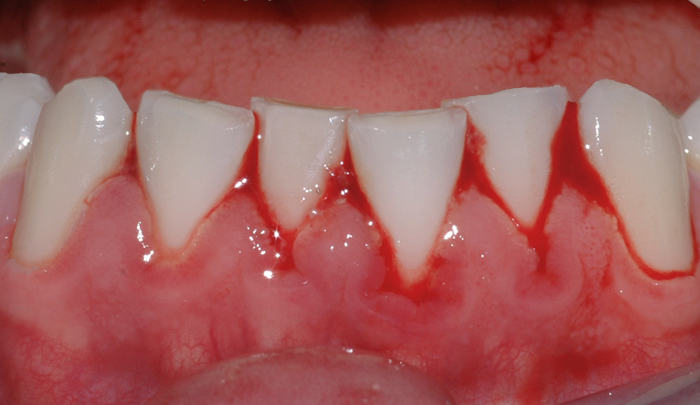

Et friskt tannkjøtt har lys rød farge og ligger stramt inntil tennene (fig. I). Et betent tannkjøtt får en mørkere rødfarge, det blir hovent og kan føles ømt ved berøring. Videre vil man kunne oppleve at tannkjøttet blør ved rengjøring og at det ligger mindre stramt inntil tennene.

Fig 1: Et friskt tannkjøtt har lys rød farge og ligger stramt inntil tennene Fig 2: Mangelfullt renhold kan over tid føre til utvikling av gingivitt

Mangelfullt renhold kan over tid føre til utvikling av gingivitt. Dette skyldes bakterier og mykt belegg (plakk) som blir liggende på tannen i kontakt med tannkjøttet (fig. II). Om man har mye tannstein, vil også dette kunne medvirke til utvikling av gingivitt. Gingivitt oppstår lettest mellom tennene og ellers der det er vanskelig å holde rent.